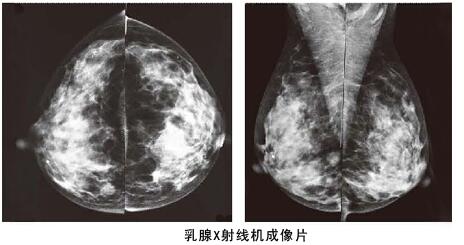

其實相比乳腺彩超,利用數字化鉬靶乳腺機對于乳腺管較細或者乳腺本身存在問題,可以進行更加細致檢查,而且它是女性乳腺癌早期診斷的金標準,數字化鉬靶乳腺機可以發現0.1毫米的鈣化點,提示癌前病變。是各種乳腺疾病檢查的必備醫療設備:如乳腺炎癥,乳腺增生,乳腺纖維瘤,乳腺囊腫等。對于一些年齡較大的女性來說,數字化鉬靶乳腺比乳腺彩超檢查更加的準確。